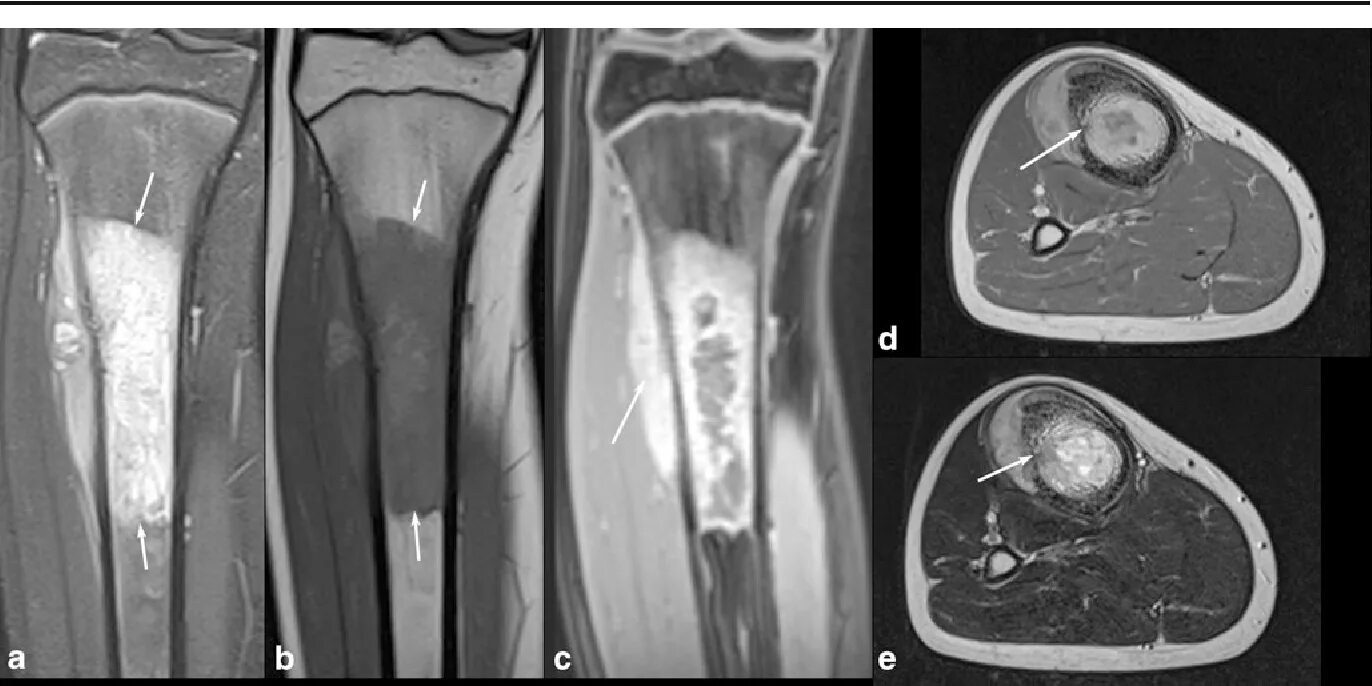

Саркома мрт